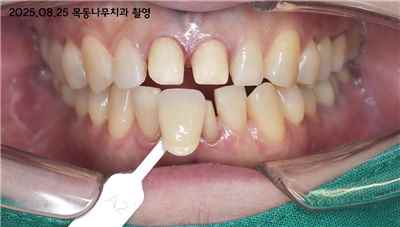

치아 변색 외부 요인

치아 변색 내부 원인